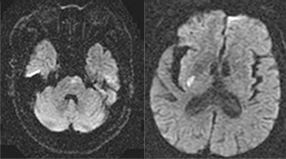

뇌혈관이 막히거나 터지는 질환을 부르는게 뇌졸중이고 그 중 뇌혈관이 막히는게 뇌경색 그리고 뇌혈관이 터지는 것을 뇌출혈이라고 합니다. 뇌졸중은 영구적인 손상이 많다고 하며 증상에 따라 전신이나 육체 일부 기능이 마비되는 등의 극심한 후유증이 남는 무서운 질병입니다 오늘은 뇌경색 초기증상에 대하여 알려드리도록 하겠습니다.

다른 뇌질환들과 달리 주변 시야가 좁아져요. 물체가 여러 개로 겹쳐 보이는 증상들이 아무런 징후도 없이 급격하게 유발돼요. 혈관이 막히면 바로 뇌 손상을 입는 환자가 있답니다. 혈관이 막혔더라도 다른 혈관으로 혈액 순환이 일정 시간 할 수 있는 환자도 있어요. 또한 혈관이 일시적으로 막혔다가 다시 뚫리면서 증세가 완화되거나 없어지는 경우도 있어요.통상 뇌경색 환자 5명 중 1명 꼴로 나타나는 증상입니다. 시력저하는 나이가 들며서 자연스럽게 나타나는 현상이라고 생각하고 쉽게지나치는 경향이 있어요. 시력 저하가 갑자기 발생하면 뇌경색을 의심할 수 있으니, 병원에 방문하시길 권해드리도록 하겠습니다.

허혈성 뇌졸중은 발생 기전에 따라 대혈관 질환에 의한 뇌경색, 심인성 뇌경색 또는 심인성 뇌경색, 소혈관 질환 또는 틈새 뇌경색, 기타 드문 이유가 되는 것에 의한 뇌경색으로 나누어져요. 에피소드는 일정 기간 동안 증상이 완전히 가라앉는 경우입니다.

허혈성 뇌졸중의 대표적인 이유가 되는 것은 고혈압, 당뇨병, 고지혈증 등으로 인해서 뇌에 혈액을 전달하는 혈관에 동맥경화(동맥경화)가 발생하여 뇌로 가는 혈류를 차단하는 것입니다.